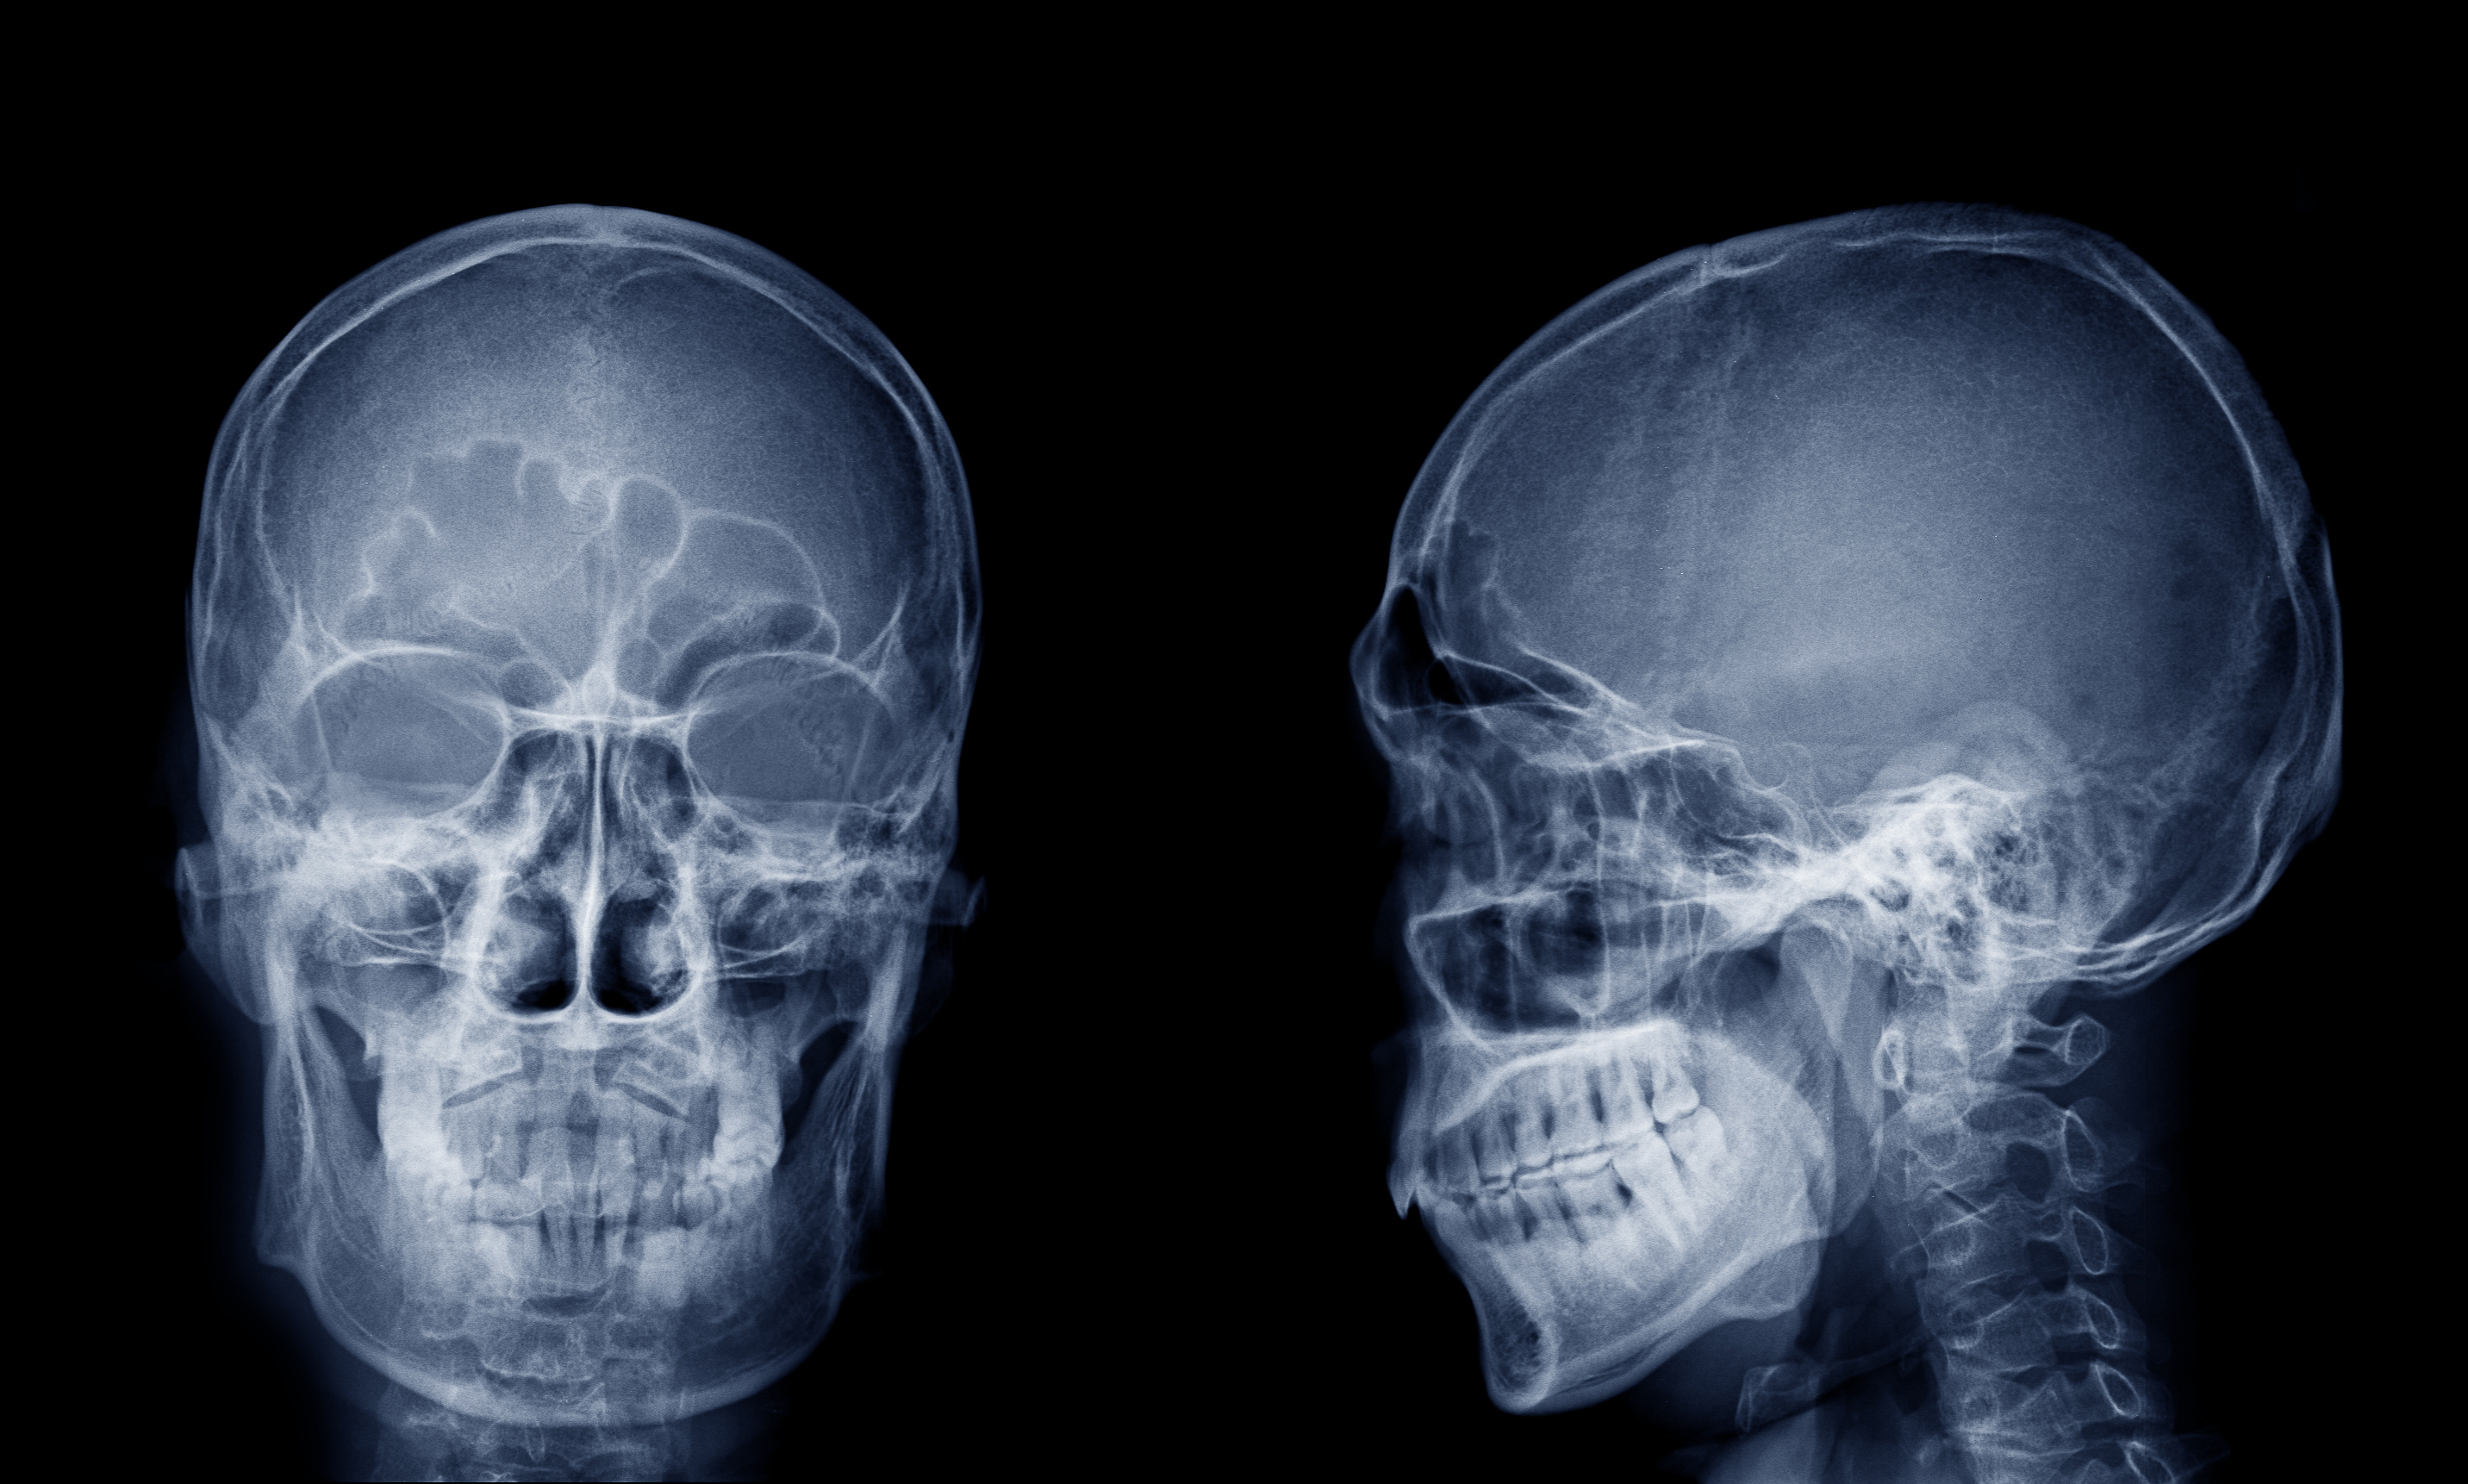

Raio-X da face em projeção frontal e lateral mostrando estruturas ósseas faciais e seios perinasais – Exame de Radiologia na Cintramédica

É um exame de rápida realização e indolor que utiliza raios X para a obtenção de uma imagem radiográfica da face.